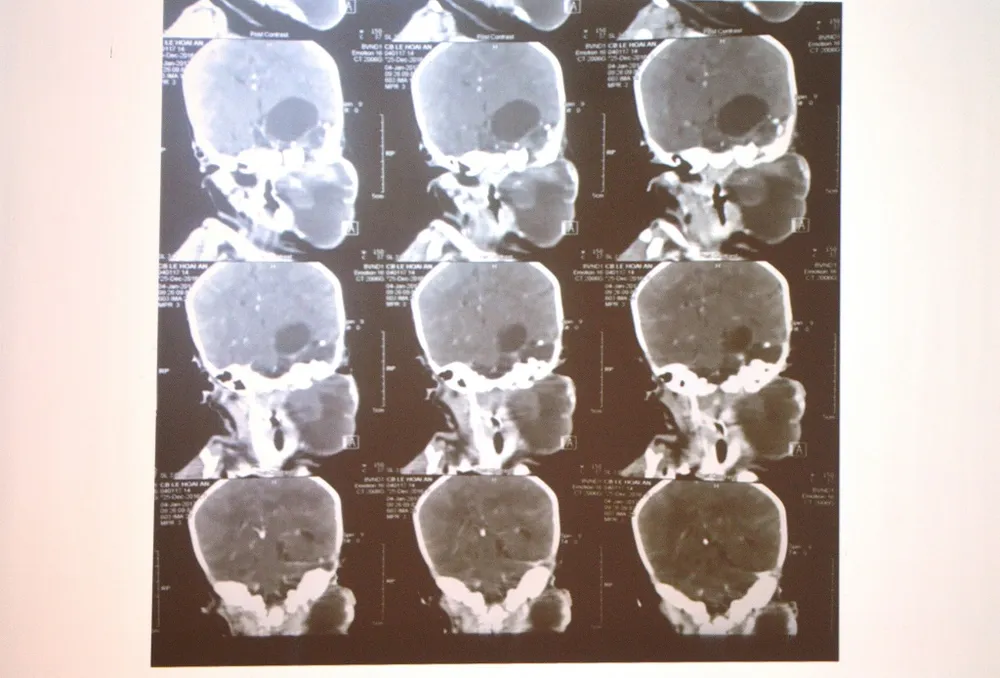

Qua chẩn đoán hình ảnh, khối bướu nằm từ góc hàm nhưng lan lên vùng nội sọ. Nếu không được phẫu thuật sớm, em bé có thể tử vong vì nguy cơ khối bướu chèn ép đường thở gây suy hô hấp hoặc chèn ép đường ăn. Mặt khác, vùng bướu lan lên nội sọ có thể tăng sinh, gây chèn ép vào phần não còn lại. Theo đánh giá, đây là một loại bướu vô cùng hiếm từ trước đến nay, y văn thế giới chỉ mới ghi nhận một trường hợp tương tự ở Mỹ và VN là trường hợp đầu tiên.

Theo BS Đào Trung Hiếu, Phó Giám đốc BV Nhi Đồng 1 cho biết, ban đầu, các bác sĩ thống nhất sẽ phối hợp 2 ê-kip  gồm bác sĩ chuyên khoa ung bướu sơ sinh và ngoại thần kinh. Bác sĩ khoa ung bướu sẽ lấy phần bướu dưới cổ trước, sau đó, bác sĩ khoa ngoại thần kinh sẽ mở sọ, lấy khối bướu vùng nội sọ.

Tuy nhiên, bước vào phòng mổ, nhận thấy khối bướu quá lớn và dính nhiều dây thần kinh. Do vậy, 2 ê-kip đã vào phòng mổ cùng một lúc và hỗ trợ nhau. Sau 7 tiếng đồng hồ khối bướu cũng được lấy ra một cách trọn vẹn. Khối bướu được lấy ra bao gồm cả phần nhân đặc, phần dịch xung quanh. Đặc biệt, khối bướu còn chứa cả tóc, xương, răng lẫn lộn.

BS Đào Trung Hiếu cho biết thêm, từ trước đến nay, bướu quái thường gặp ở cơ quan sinh dục. Bé nữ thường gặp ở buồng trứng, bé nam thường ở tinh hoàn. Bướu quái tại vị trí xương cùng cụt và vùng trung thất ít gặp hơn. Bướu quái vùng cổ và vùng nội sọ là rất ít gặp. Em bé này mang một khối bướu quái vùng cổ lan lên nội sọ là trường hợp vô cùng hiếm gặp. Từ trước đến nay, y văn thế giới chỉ mới ghi nhận 1 ca tương tự vào năm 2004 ở Mỹ.